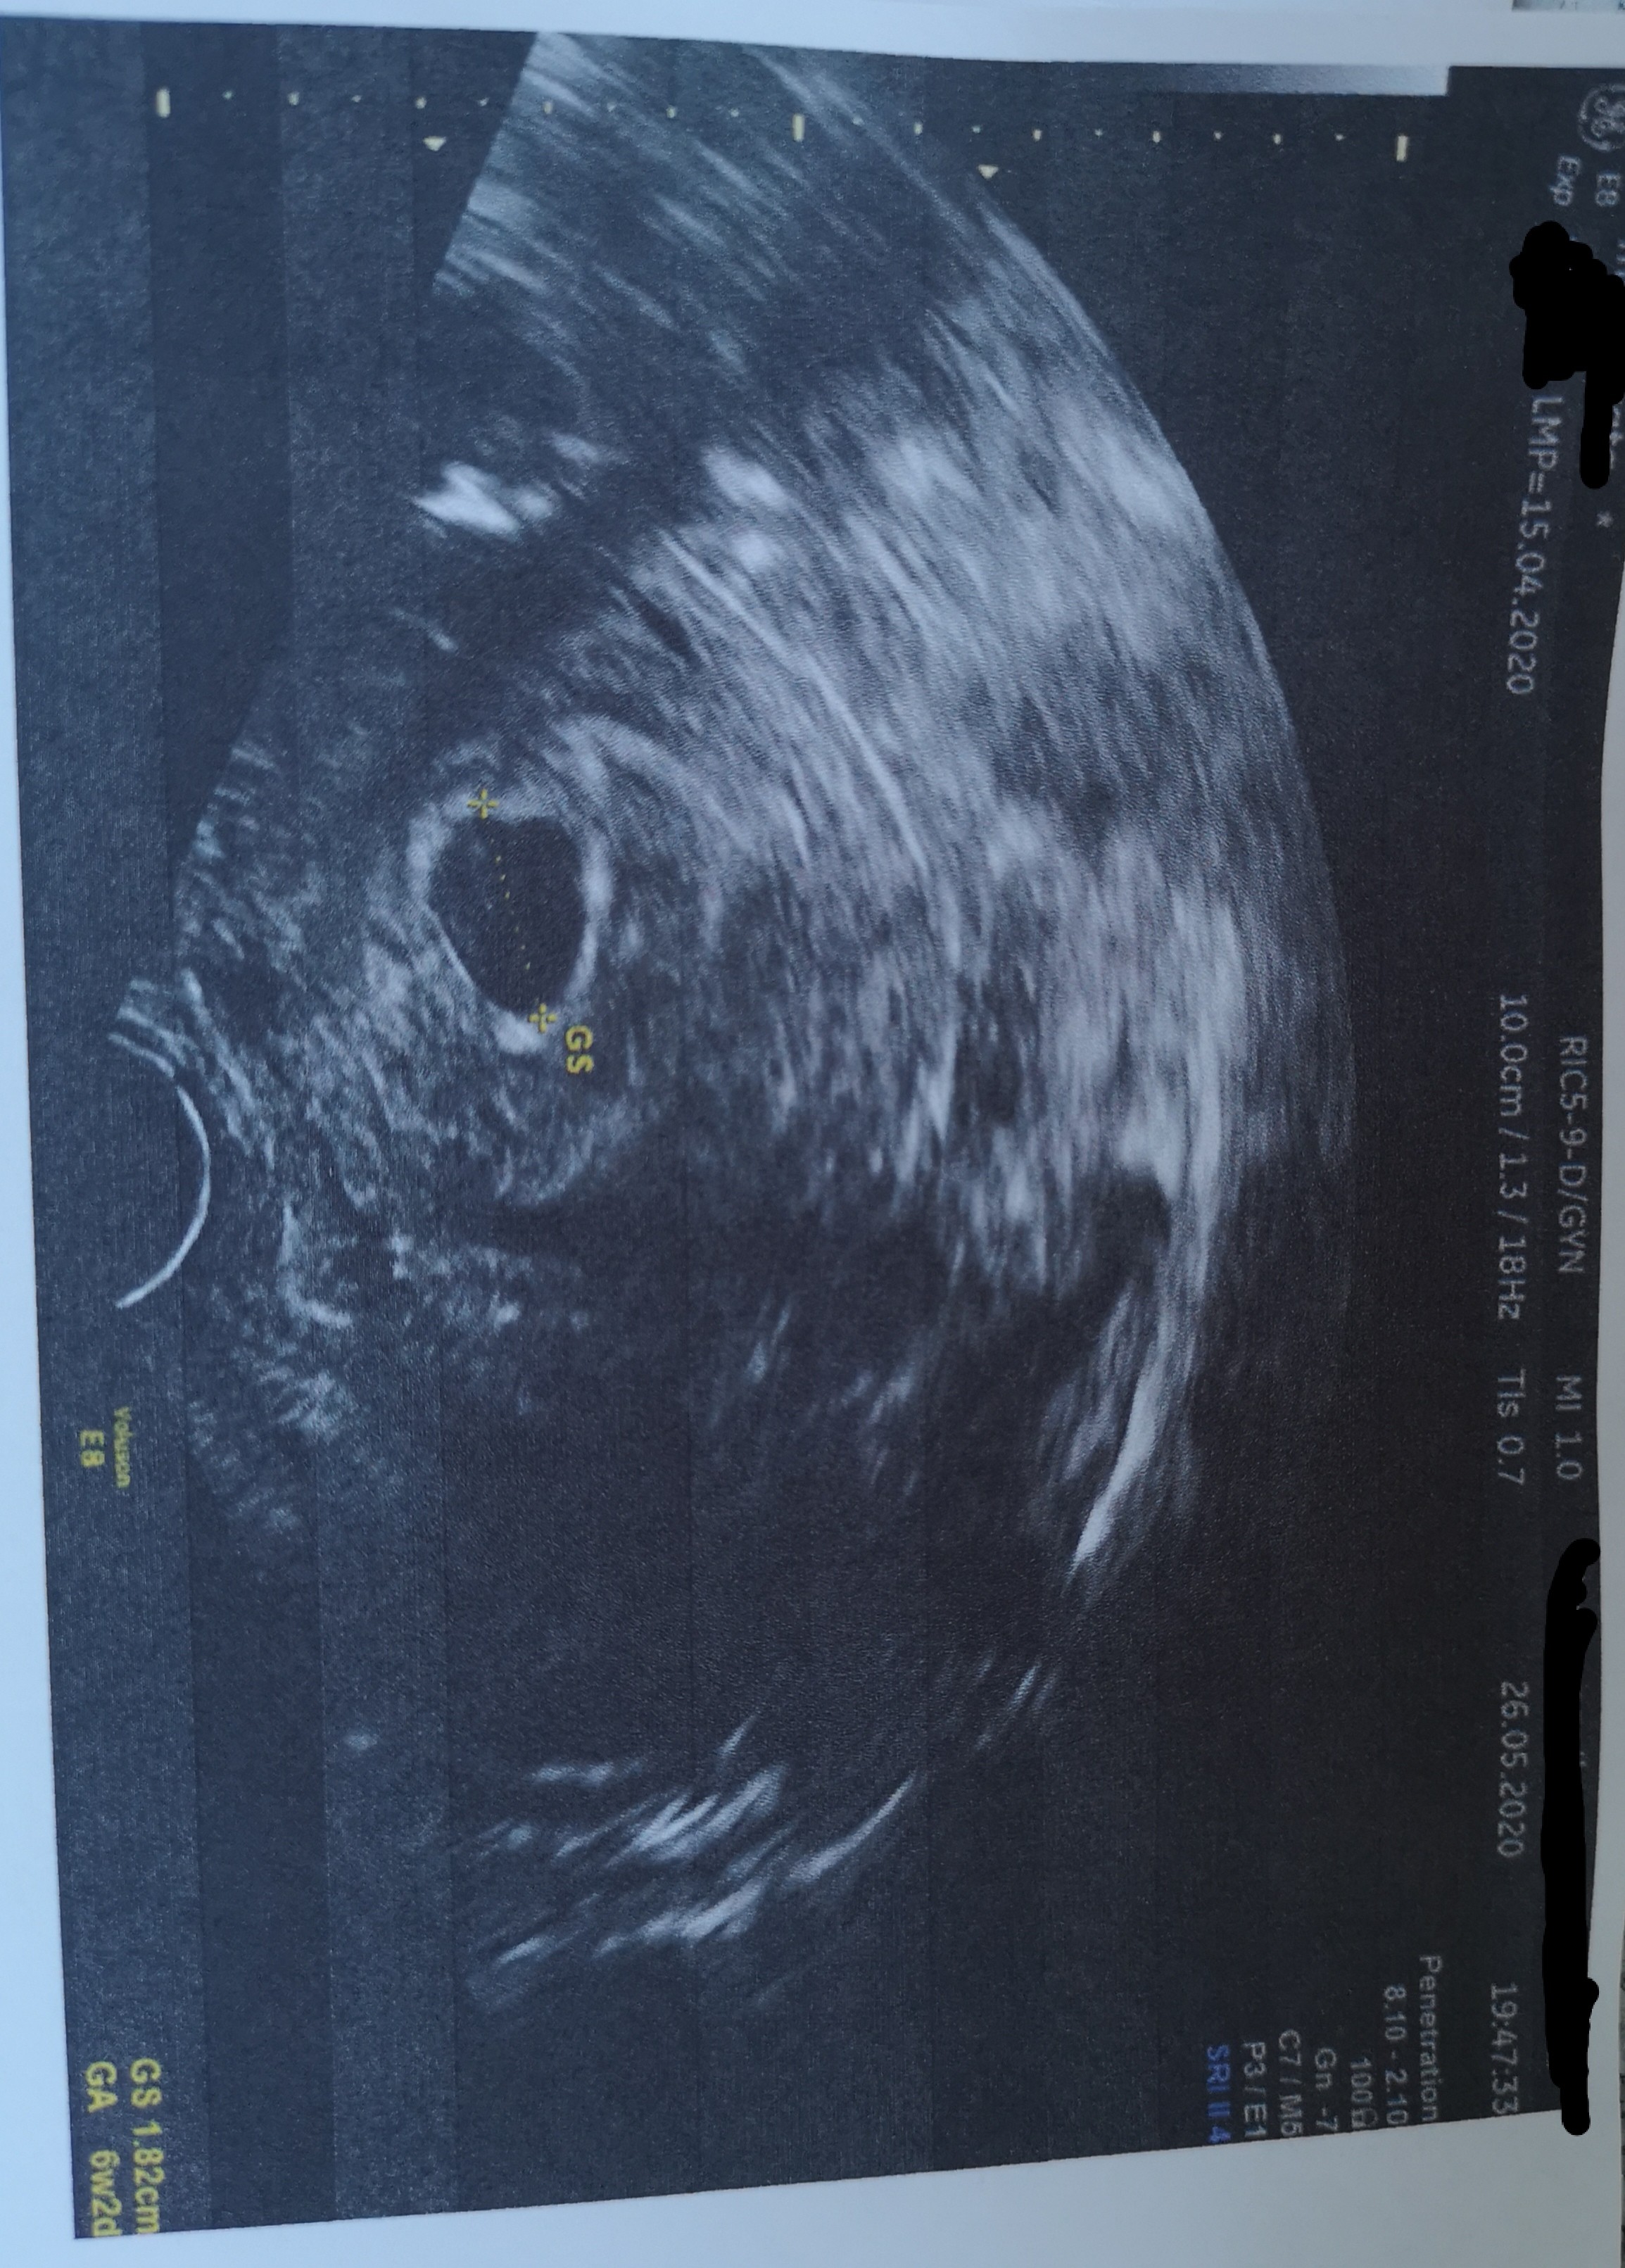

Cześć, chciałabym dołączyć. Termin porodu 7-9 stycznia wg roznych aplikacji. Wczoraj byłam na pierwszej wizycie, termin z om zgadza się prawie idealnie z usg 7+5, bije serduszko, ale lekarka nie podała mi terminu porodu ani nie założyła karty ciąży, podała jedynie listę badań na następną wizytę. Zauważyła też beżowe plamienie i zapisała duphaston w razie jakby pojawiło się go więcej lub byłyby bole podbrzusza